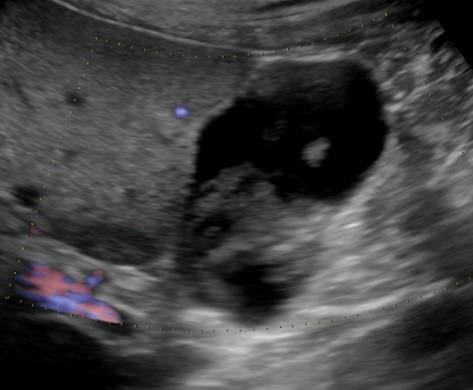

Bùn túi mật

» Thông tin: Nam giới – 60 tuổi.

» Lâm sàng: Đau mạn sườn phải.